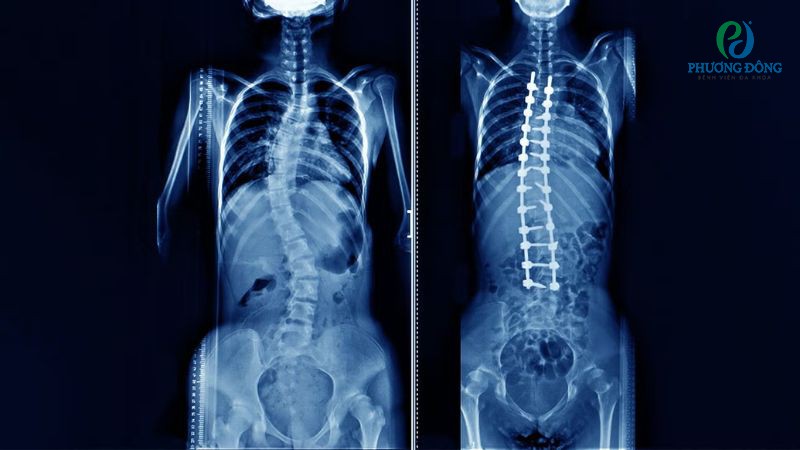

- Cột sống cong vẹo, biến dạng.

Mổ gai cột sống là phương pháp ngoại khoa cắt bỏ hoàn toàn gai xương, giải quyết triệt để tình trạng tủy sống hoặc hệ thống dây thần kinh bị chèn ép. Cuộc phẫu thuật được thực hiện khi có chỉ định từ bác sĩ chuyên khoa, cân nhắc kỹ lưỡng dựa trên các kết quả khám lâm sàng và cận lâm sàng.